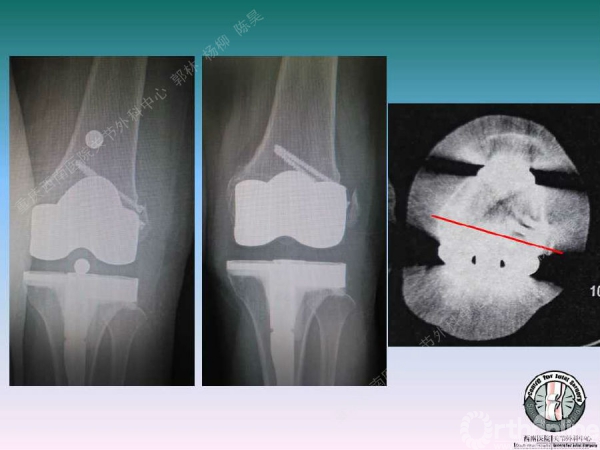

导读:文中,来自重庆西南医院的郭林教授为大家介绍了股骨冠状位关节外畸形的TKA的相关知识,并详细阐述了关节外畸形的概念、诊断、关节内滑移截骨技术等相关内容。

滑移截骨纠正关节外畸形

关节内滑移截骨的缺点和并发症